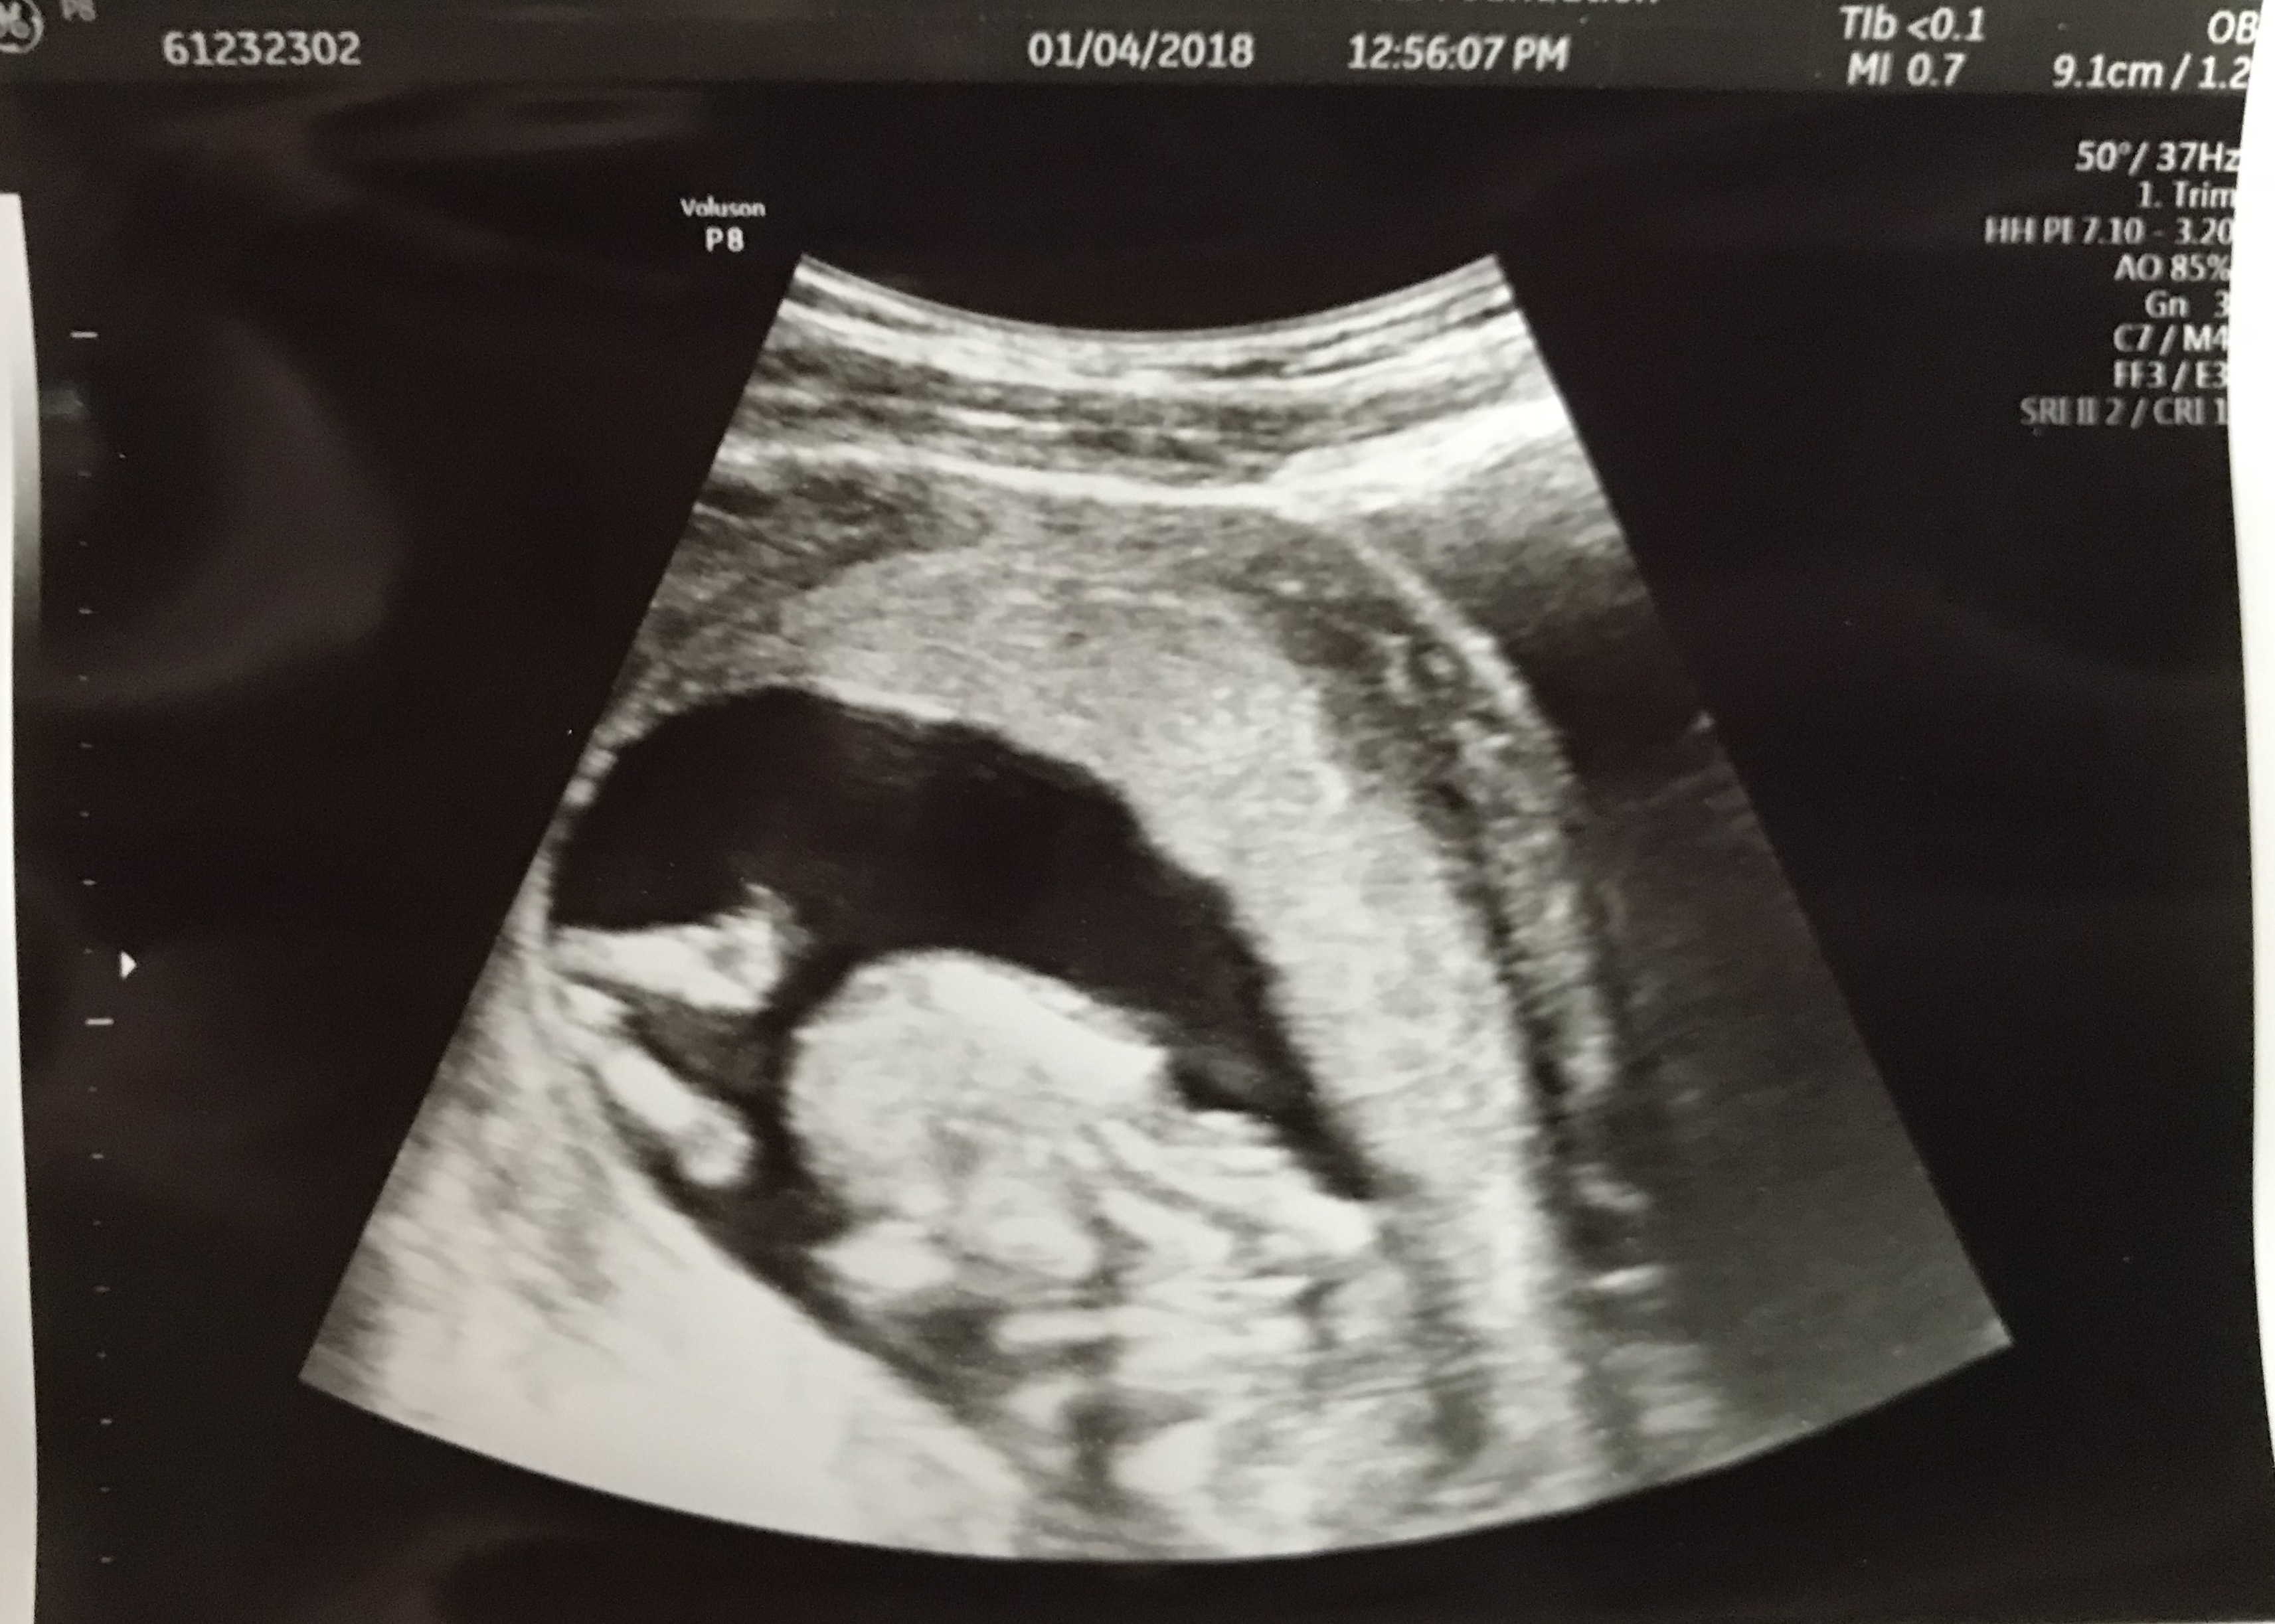

Again, the two week wait for the next appointment felt like eternity. I was praying that the baby would be healthy with a strong heartbeat. This was technically considered my first OB appointment– it was a long one because she did a complete physical exam and went over all of the first trimester tests/bloodwork before the ultrasound. Finally, it was time to see our baby. Right away we were able to see the heartbeat. I was now able to fully focus on what the doctor was saying. Thankfully, my hubby was there to comprehend everything that was said before the ultrasound was done. The baby measured a few days ahead of schedule and was actually starting to look like a baby.

At my last appointment I thought I was 12 weeks, but baby measured to be 13w1d. One week ahead of schedule. Moore babe is growing like a champ. It was amazing to see how active the baby was. That little thing was squirming all around during the ultrasound. Our doctor measured the fluid and the baby and was pleased with the results. Baby’s heartbeat was at 163. Hearing the heartbeat was priceless. Hubby was able to get it on video. Something we will cherish forever. Baby actually looked like a baby. The arms, legs, spine, head and body were all very distinct. We were at ease walking out of this appointment. It was wonderful hearing the strong heartbeat and seeing all of the movement. I’m on the first trimester mend where my energy is slowly coming back and my nausea/sickness is not nearly as bad. Hello second trimester! Happy Monday!